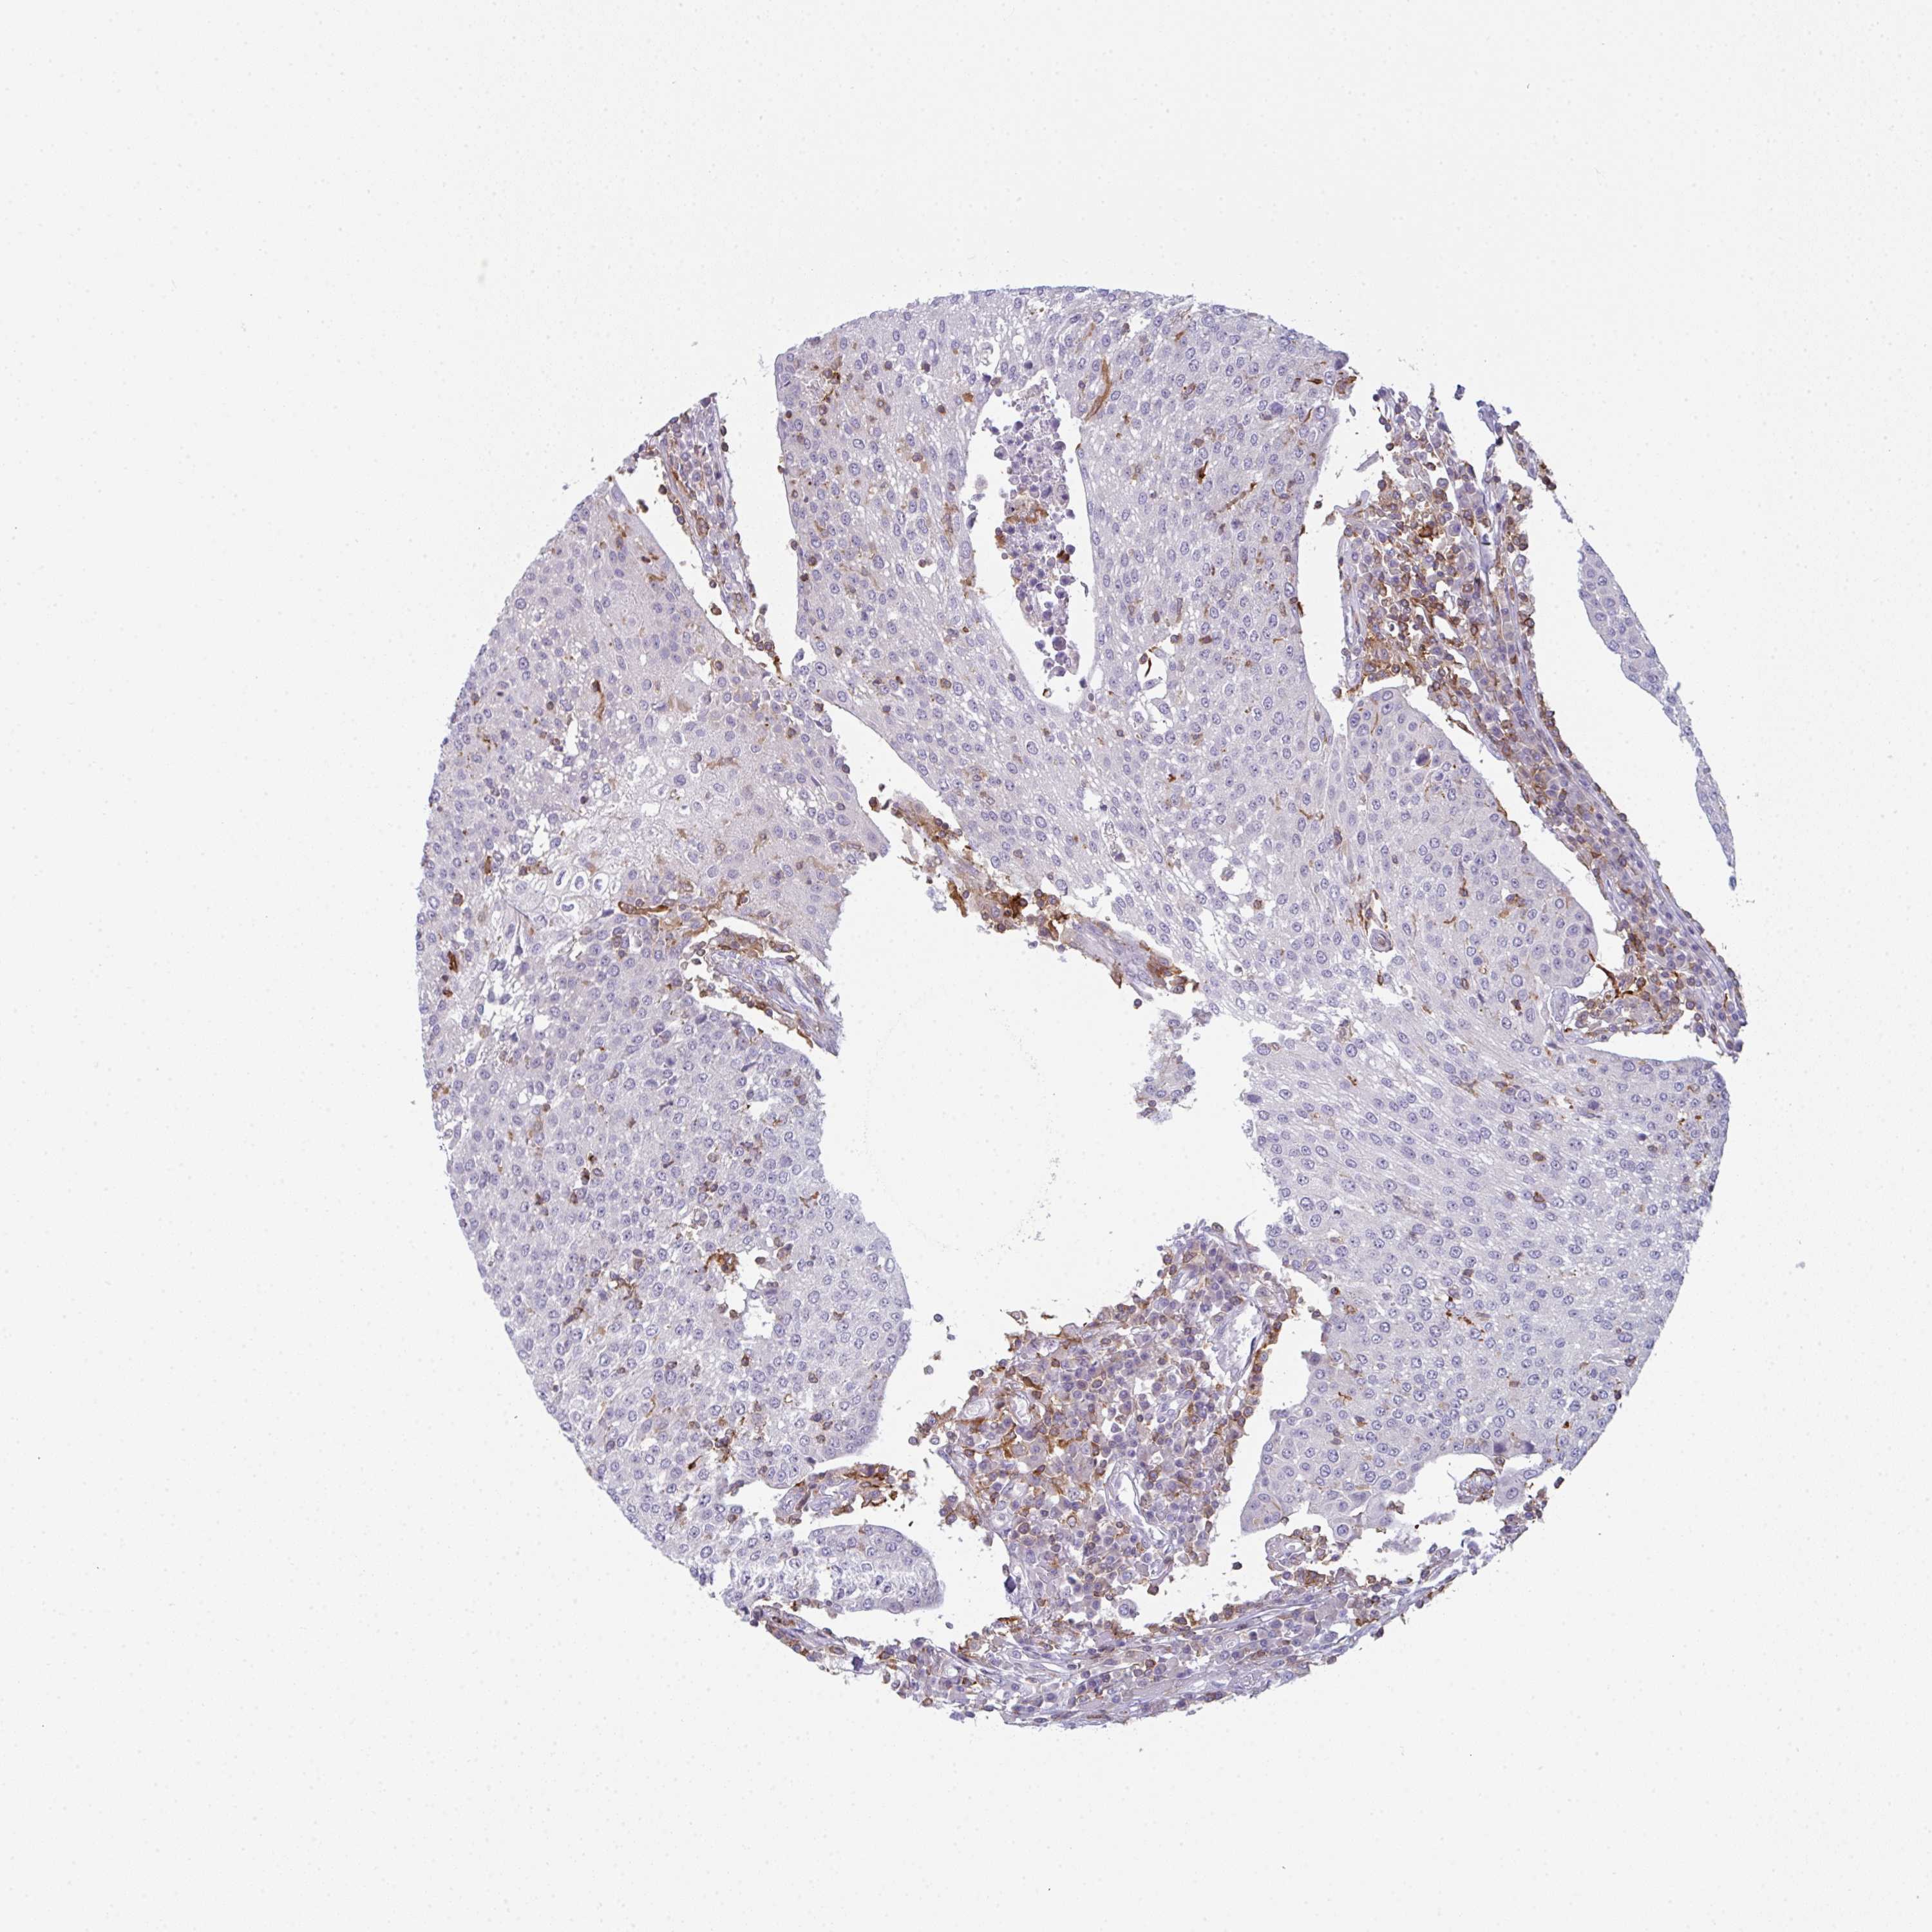

UROTHELIAL CANCER - Protein expressioni

A mouse-over function shows sample information and annotation data. Click on an image to view it in a full screen mode. Samples can be filtered based on level of antibody staining by selecting one or several of the following categories: high, medium, low and not detected. The assay and annotation is described here.

Note that samples used for immunohistochemistry by the Human Protein Atlas do not correspond to samples in the TCGA dataset.

Antibody stainingi

Antibody staining in the annotated cell types in the current human tissue is reported as not detected, low, medium, or high, based on conventional immunohistochemistry profiling in selected tissues. This score is based on the combination of the staining intensity and fraction of stained cells.

Each image is clickable and will lead to virtual microscopy that enables deeper exploration of all samples and also displays staining intensity scores, fraction scores and subcellular localization as well as patient and tissue information for each sample.

Antibody HPA050092

Antibody CAB025368

Urothelial carcinoma, High grade

Urothelial carcinoma, Low grade